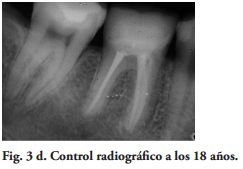

Los exámenes clínicos fueron realizados con un espejo y un explorador agudo. Un control radiográfico fue hecho en cada DPET. La evaluación de las variables relacionada a las restauraciones, fue ciega entre los autores. El Coeficiente Kappa de Cohen (14), en la calidad de las restauraciones y del examen radiográfico, varió de 0.78 a 1 [excelente de acuerdo a la guía de Fleiss (15). En los casos de no concordancia en la calificación, se registró el valor más bajo.

Al momento del examen, 10 (90.9%) EC estaban en función en 10 pacientes. Un molar 26, restaurado con EC, se perdió por enfermedad periodontal después de 12 años y 9 meses en función. Ninguna restauración se desprendió, no hubo recidiva de caries y al examen radiográfico no se observaron lesiones patológicas en los 10 DPET en función (Figs. 1a,1d; 2c; 3c,3d; 4c).

Los resultados de este estudio, mostraron un patrón de desvío estandar de 3 años y 11 meses (95% CI, 2 años y 10 meses - 6 años y 5 meses).